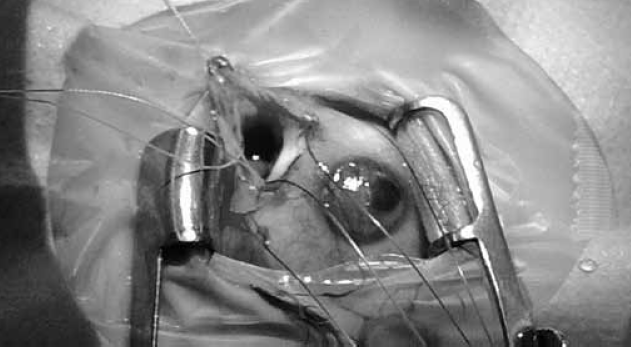

По результатам обследования выставлен диагноз «киста зрительного нерва», вероятнее всего, также колобоматозной природы. Учитывая наличие лагофтальма, приведшего к развитию ксероза роговицы с угрозой ее перфорации, было принято решение об оперативном лечении. В целях получения быстрого результата, с одной стороны, при минимальной инвазивности вмешательства — с другой, запланирована пункция и дренирование кисты зрительного нерва.

Произведена трансконъюнктивальная орбитотомия через верхний конъюнктивальный свод, мобилизован участок стенки кисты (рис. 7), после пункции получено 7 мл жидкости светло-желтого цвета. Выполнено цитологическое исследование полученного содержимого кисты — соломенно-желтая, прозрачная, белок 2,74 г/л, глюкоза 1,6 ммоль/л, цитоз 34/3. Цитоз представлен нейтрофилами, лимфоцитами, единичными макрофагами и неизмененными эритроцитами. От спинномозговой жидкости содержимое кисты отличалось значительно более высоким содержанием белка (в норме в ликворе до 0,33 г/л), низким уровнем глюкозы (в ликворе 2,8–3,9 ммоль/л) и высоким содержанием клеток (цитоз ликвора в норме 6–9/3).

Рис. 7. Ревизована колобоматозная киста правой глазницы, которая затем была пунктирована